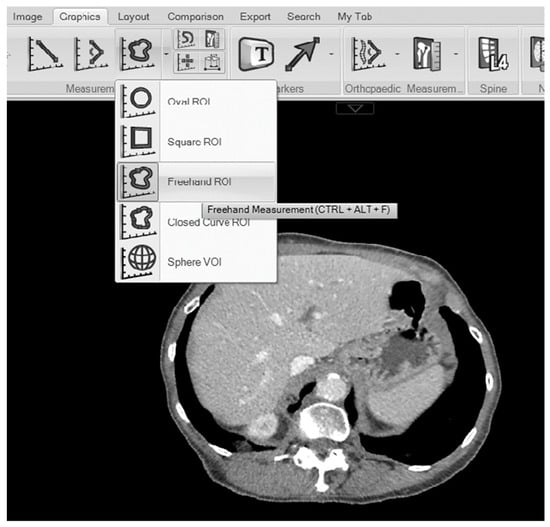

2.2. Measurements of the Maximal Liver Area and Total Liver Volume